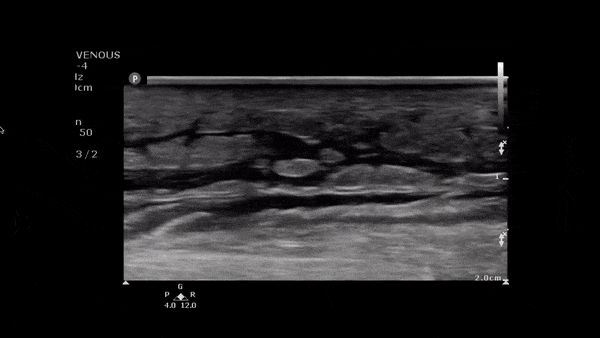

Soft Tissue - Cobblestoning in Cellulitis

This image demonstrates anechoic fluid surrounding islands of soft tissue. In the setting of infectious signs and symptoms this is consistent with a cellulitis. Image obtained from 5 Minute Sono.